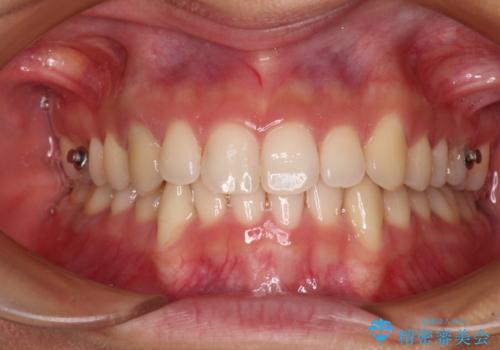

【モニター】下顎の気になる八重歯を改善 インビザラインによる矯正治療

- 下顎の八重歯を気にして来院された患者様です。

マウスピース矯正でもワイヤー矯正でも対応可能であり、マウスピースによる治療を希望されたため、インビザラインを用いることとしました。

下顎前歯にデコボコが集中していたため、顎間ゴムによる後方移動とIPR(歯と歯の間を削ること)により歯列を整えることとしました。

しっかりとマウスピースを装着してくださったおかげで、スムーズに治療を終えることができました。